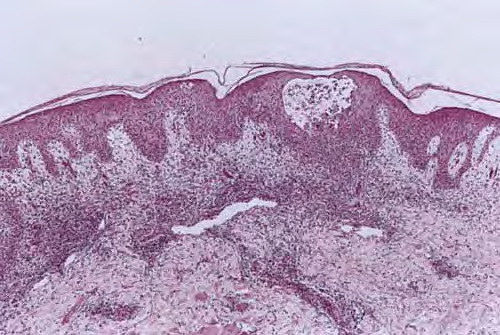

Herpes simplex = العقبول البسيط